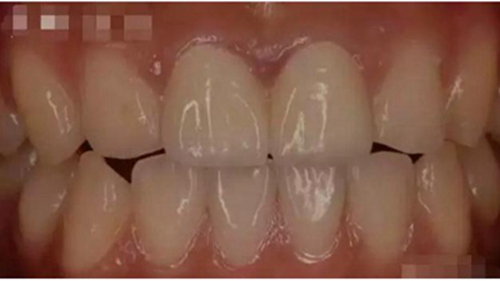

這幾天,一張照片刷爆了牙醫(yī)朋友圈

對(duì)這張照片,有牙醫(yī)評(píng)論如下:

口內(nèi)有金屬烤瓷牙做核磁共振,CT,以烤瓷牙為中心呈現(xiàn)放射狀影像,無法看清周圍組織,影響臨床診斷,建議條件允許的朋友還是選擇二氧化鋯全瓷冠修復(fù),以免帶來不必要的麻煩!